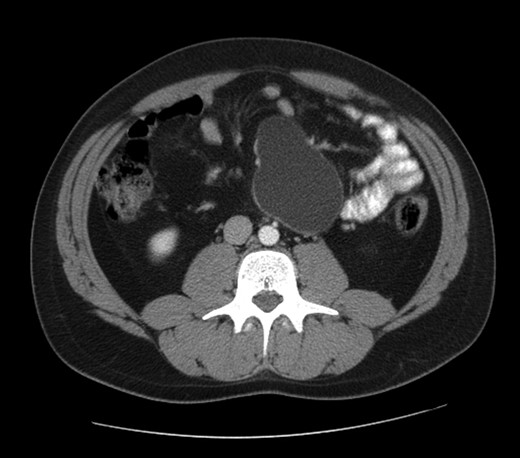

The abdominal computed tomography scan with contrast revealed a huge (10 cm of diameter) retroperitoneal cyst, oval shaped and containing dense fluid, located within the caval vein and the aorta, under the origin of the renal artery, partially dislocating the caval vein to the right (see Fig. 2).

Computed tomography view of the mesenteric cyst partially dislocating the caval vein.